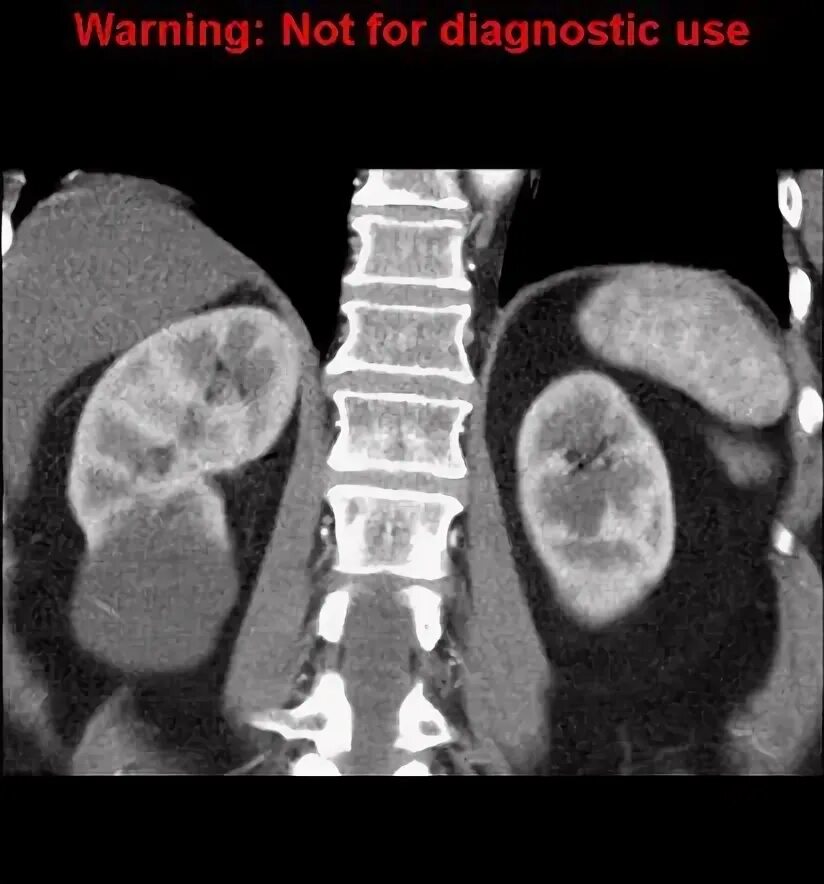

Кисты почек bosniak